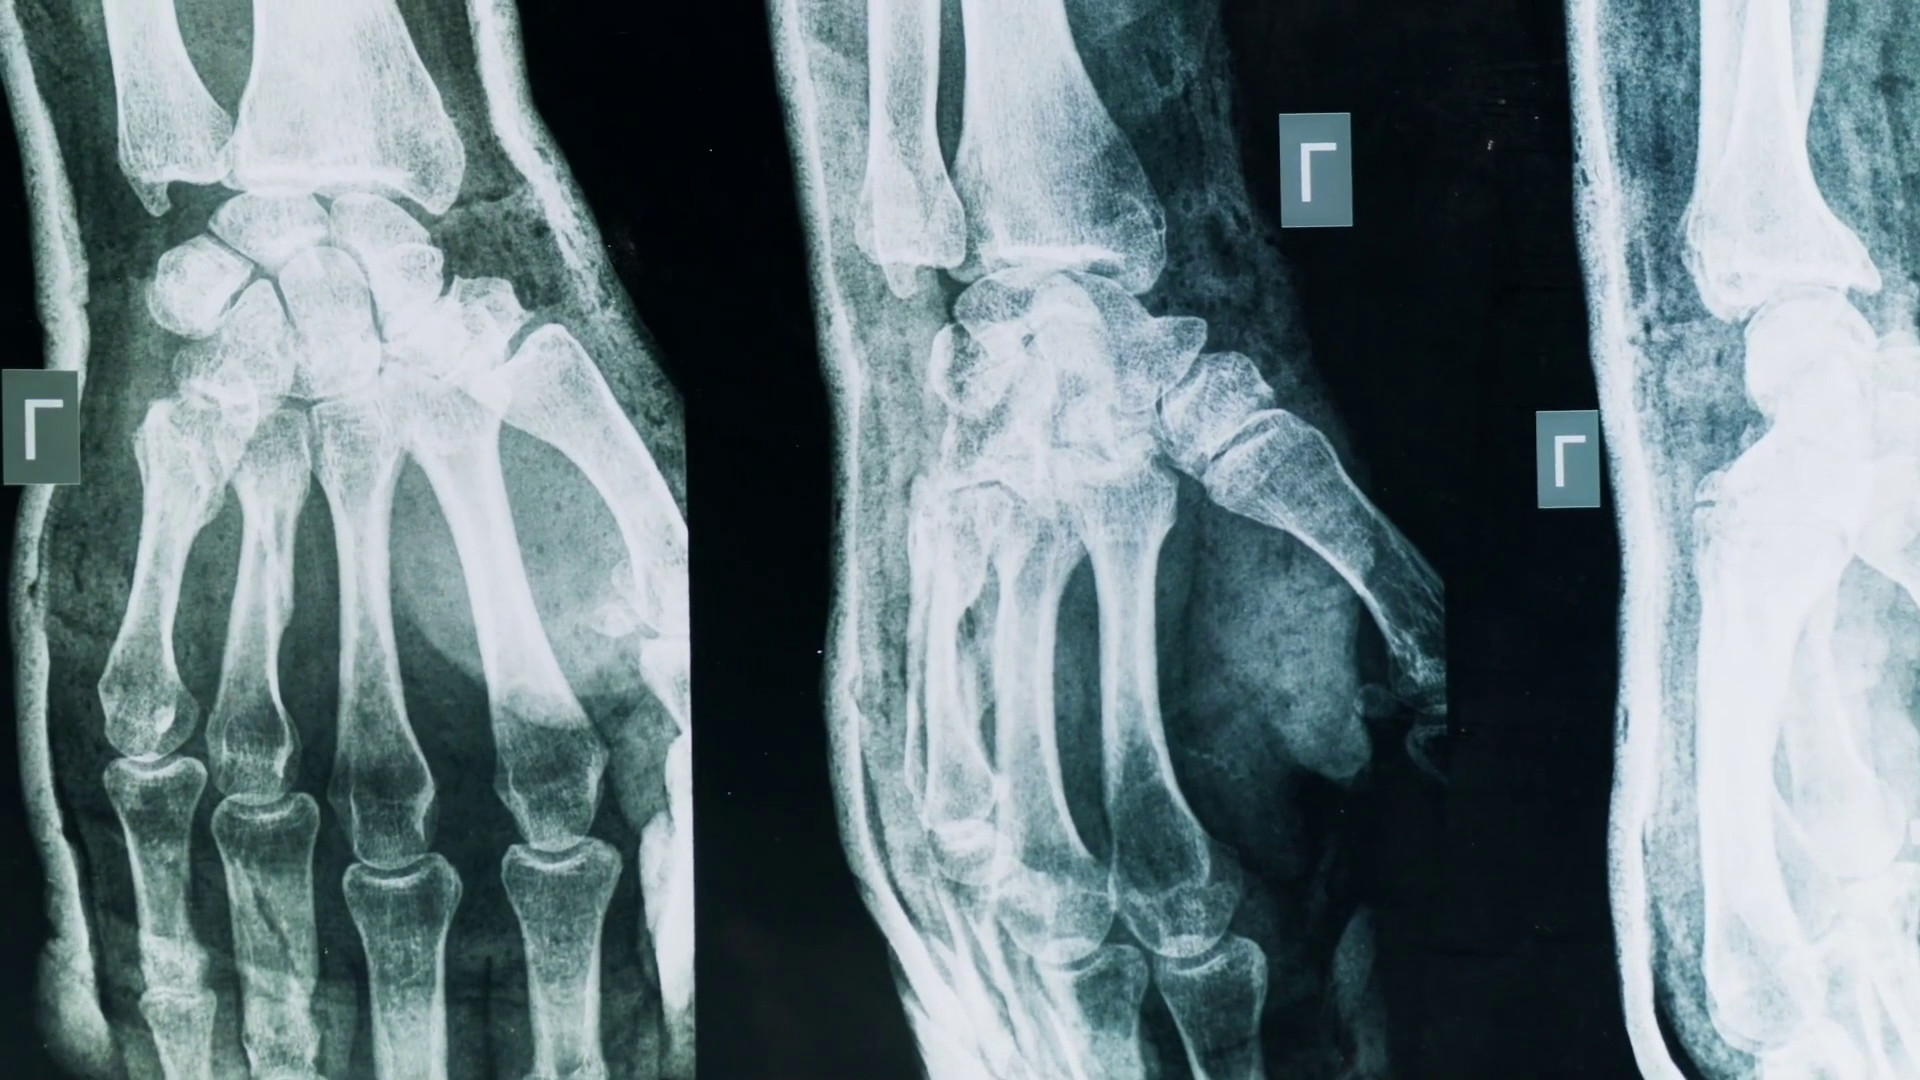

MILANO (ITALPRESS) – Artrite e artrosi sono tra le più diffuse malattie articolari: due condizioni che condividono alcuni sintomi ma differiscono per causa, evoluzione e trattamento. Con il termine artrite si intende un gruppo di malattie infiammatorie delle articolazioni: può avere origine autoimmune, infettiva o essere legata ad altre malattie sistemiche. Una delle forme più studiate è l’artrite reumatoide, che si manifesta con infiammazione persistente, dolore e gonfiore e può colpire più articolazioni in modo simmetrico: in Italia si stima che l’artrite reumatoide colpisca circa 400mila persone. Al contrario l’artrosi è una malattia degenerativa, caratterizzata dall’usura della cartilagine articolare, alterazioni della struttura ossea sottocartilaginea e cambiamenti delle cellule articolari. È la forma più comune di malattia articolare: i principali fattori di rischio sono l’età, il sovrappeso, il sovraccarico articolare, traumi pregressi, predisposizioni genetiche.

“Quando una persona arriva con dolore a un’articolazione questo si definisce un’artralgia, quindi un semplice dolore; se c’è un’articolazione degenerata parleremo di artrosi, mentre se è infiammata parleremo di artrite. Sono dolori di tipo molto diverso: quello dell’artrosi peggiora con l’uso e il carico dell’articolazione, quello dell’artrite con l’inattività”, ha dichiarato Carlo Selmi, responsabile dell’unità operativa di Reumatologia e Immunologia clinica presso l’ospedale Humanitas di Rozzano, intervistato da Marco Klinger per Medicina Top, format tv dell’agenzia di stampa Italpress.